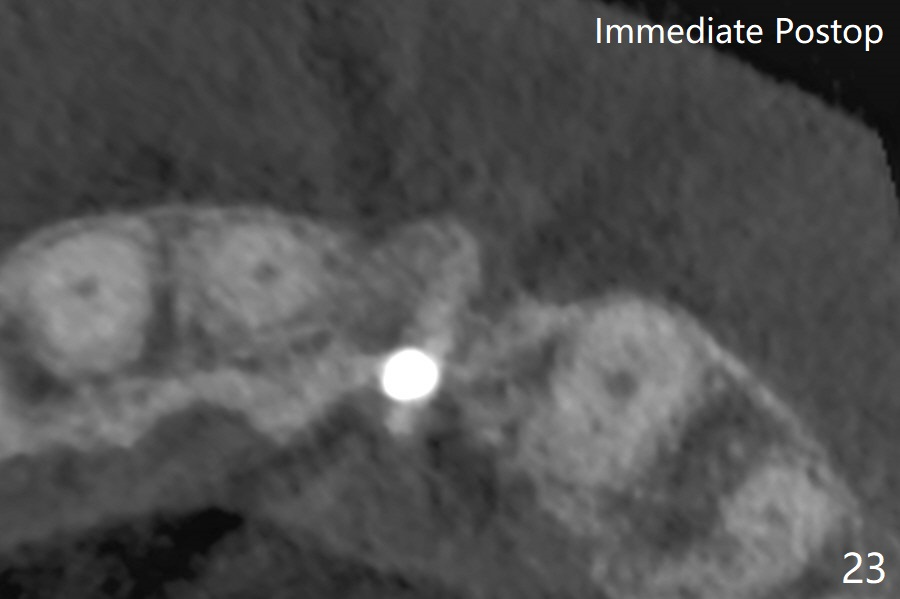

病人回来带来瘘道(图一),不过不会增加难度,病牙去除,它便自动消失。尽管颊侧骨壁完全失去,颊侧牙龈仍丰满(图二),为什么呢?第一,因为粗大牙根存在,第二两旁牙齿,牙槽骨撑着帐篷(侧切牙颊侧牙龈),第三,牙冠。为了防止术后牙龈塌陷,尽量不切开,即刻放置植体(牙根);由于前牙缘故,这次植体不能很大,所以植骨必须过度(over grafting),最后即刻制作临时牙冠,撑住牙龈。这就是所谓每个人进入角色。这个牙根有一种先天性畸形:dens in dent (图三(腭侧观):箭头)。尽管腭侧牙根畸形,腭侧骨壁吸收临床上并不严重,所以钻洞仍偏腭侧。当预定最后钻头还在钻洞时,填入大量粘性骨块(图四:*),细长植体还没有完全卡入鼻底(图五),最后好像可以(图六,七)。植体,骨粉入位(图八),最后临时牙冠出场(图九)。尽管植体小,术后一周临时牙冠仍然可以维持牙龈原有形状(emergency profile,图十:箭头(*:树脂强化牙冠固定))。图十一以不同角度显示瘘道缩小。术后三周取出有些松动的临时牙冠,骨粉虽然还没有被肉芽组织整合,但是显得正常,周围牙龈健康(图十二)。术后4个月牙龈形态正常(图十三),没有触痛;颊侧骨板轻度凹陷(图十四);骨粉仍在原位(图十五)。术后7个月骨粉仍在原位(图十五,十六,但是冠部密度减低(可能骨粉流失,需要牙周或者树脂敷料保护)),没有螺纹暴露。但是牙冠边缘暴露,说明牙龈收缩(图十七,与图十三对比),颊侧骨板仍塌陷(图十八)。插入龈线取得多个目的:修整基台边缘,取模,颊侧牙龈推向颊侧,有利于即将衬里牙冠龈缘进入龈下(图十九)。取模后牙冠边缘(图二十:<)衬里,然后修整,变窄,以便插入龈下,促进颊侧牙龈下降(图二十一,二十二)。术后8个月牙冠粘固前牙龈健康(图二十七,八),牙冠(图二十九)固位后,病人满意(图三十),咬合调整(图三十一),注意腭侧粘固粉流出通道(<)。